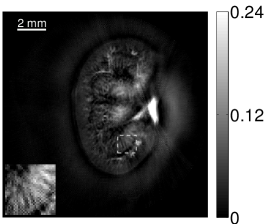

VI-E Results: kidney phantom

The images and EIRs reconstructed by use of the VP algorithm that was based on the 2D imaging model that neglected the SIR are shown in Figures 15 and 16. The latter figure contains results corresponding to different values for the regularization parameter . From Fig. 15, it can be observed that use of the conventional iterative method that utilized the measured EIR resulted in distortions and loss of details in the reconstructed images. Use of the VP algorithm improved the contrast and the details in the reconstructed images (Fig. 15(c) and 16(a)). Furthermore, the images reconstructed by use of the VP algorithm had a more uniform background.

In Figure 17, the results corresponding to use of the 3D imaging model that incorporated SIR effects are shown. The EIR estimated by the VP algorithm is also shown. In Figure 18, images and EIRs reconstructed by use of the VP algorithm with different regularization parameters values are shown.

Similar to the case described above where the transducer SIR was neglected, these results reveal that use of the VP algorithm can produce images with a cleaner background and enhanced spatial resolution than yielded by use of a conventional iterative algorithm that employed the measured EIR. For example, detailed information regarding the vessels near the organ’s periphery was better preserved by the VP algorithm than by the conventional iterative algorithm. These images corroborate our assertion that the VP algorithm can significantly reduce the artifacts and distortions in the reconstructed image. It is also worth pointing out that, unlike the numerical phantom studies, the artifacts and distortions in the images may be caused not only by the inaccurate EIR but also by other factors, such as neglecting acoustic heterogeneities and the variation of the EIRs among the elements of the transducer array. In such cases, the EIR estimated by the VP algorithm represents an effective system impulse response that minimizes the inconsistency between the measured data and the imaging model.